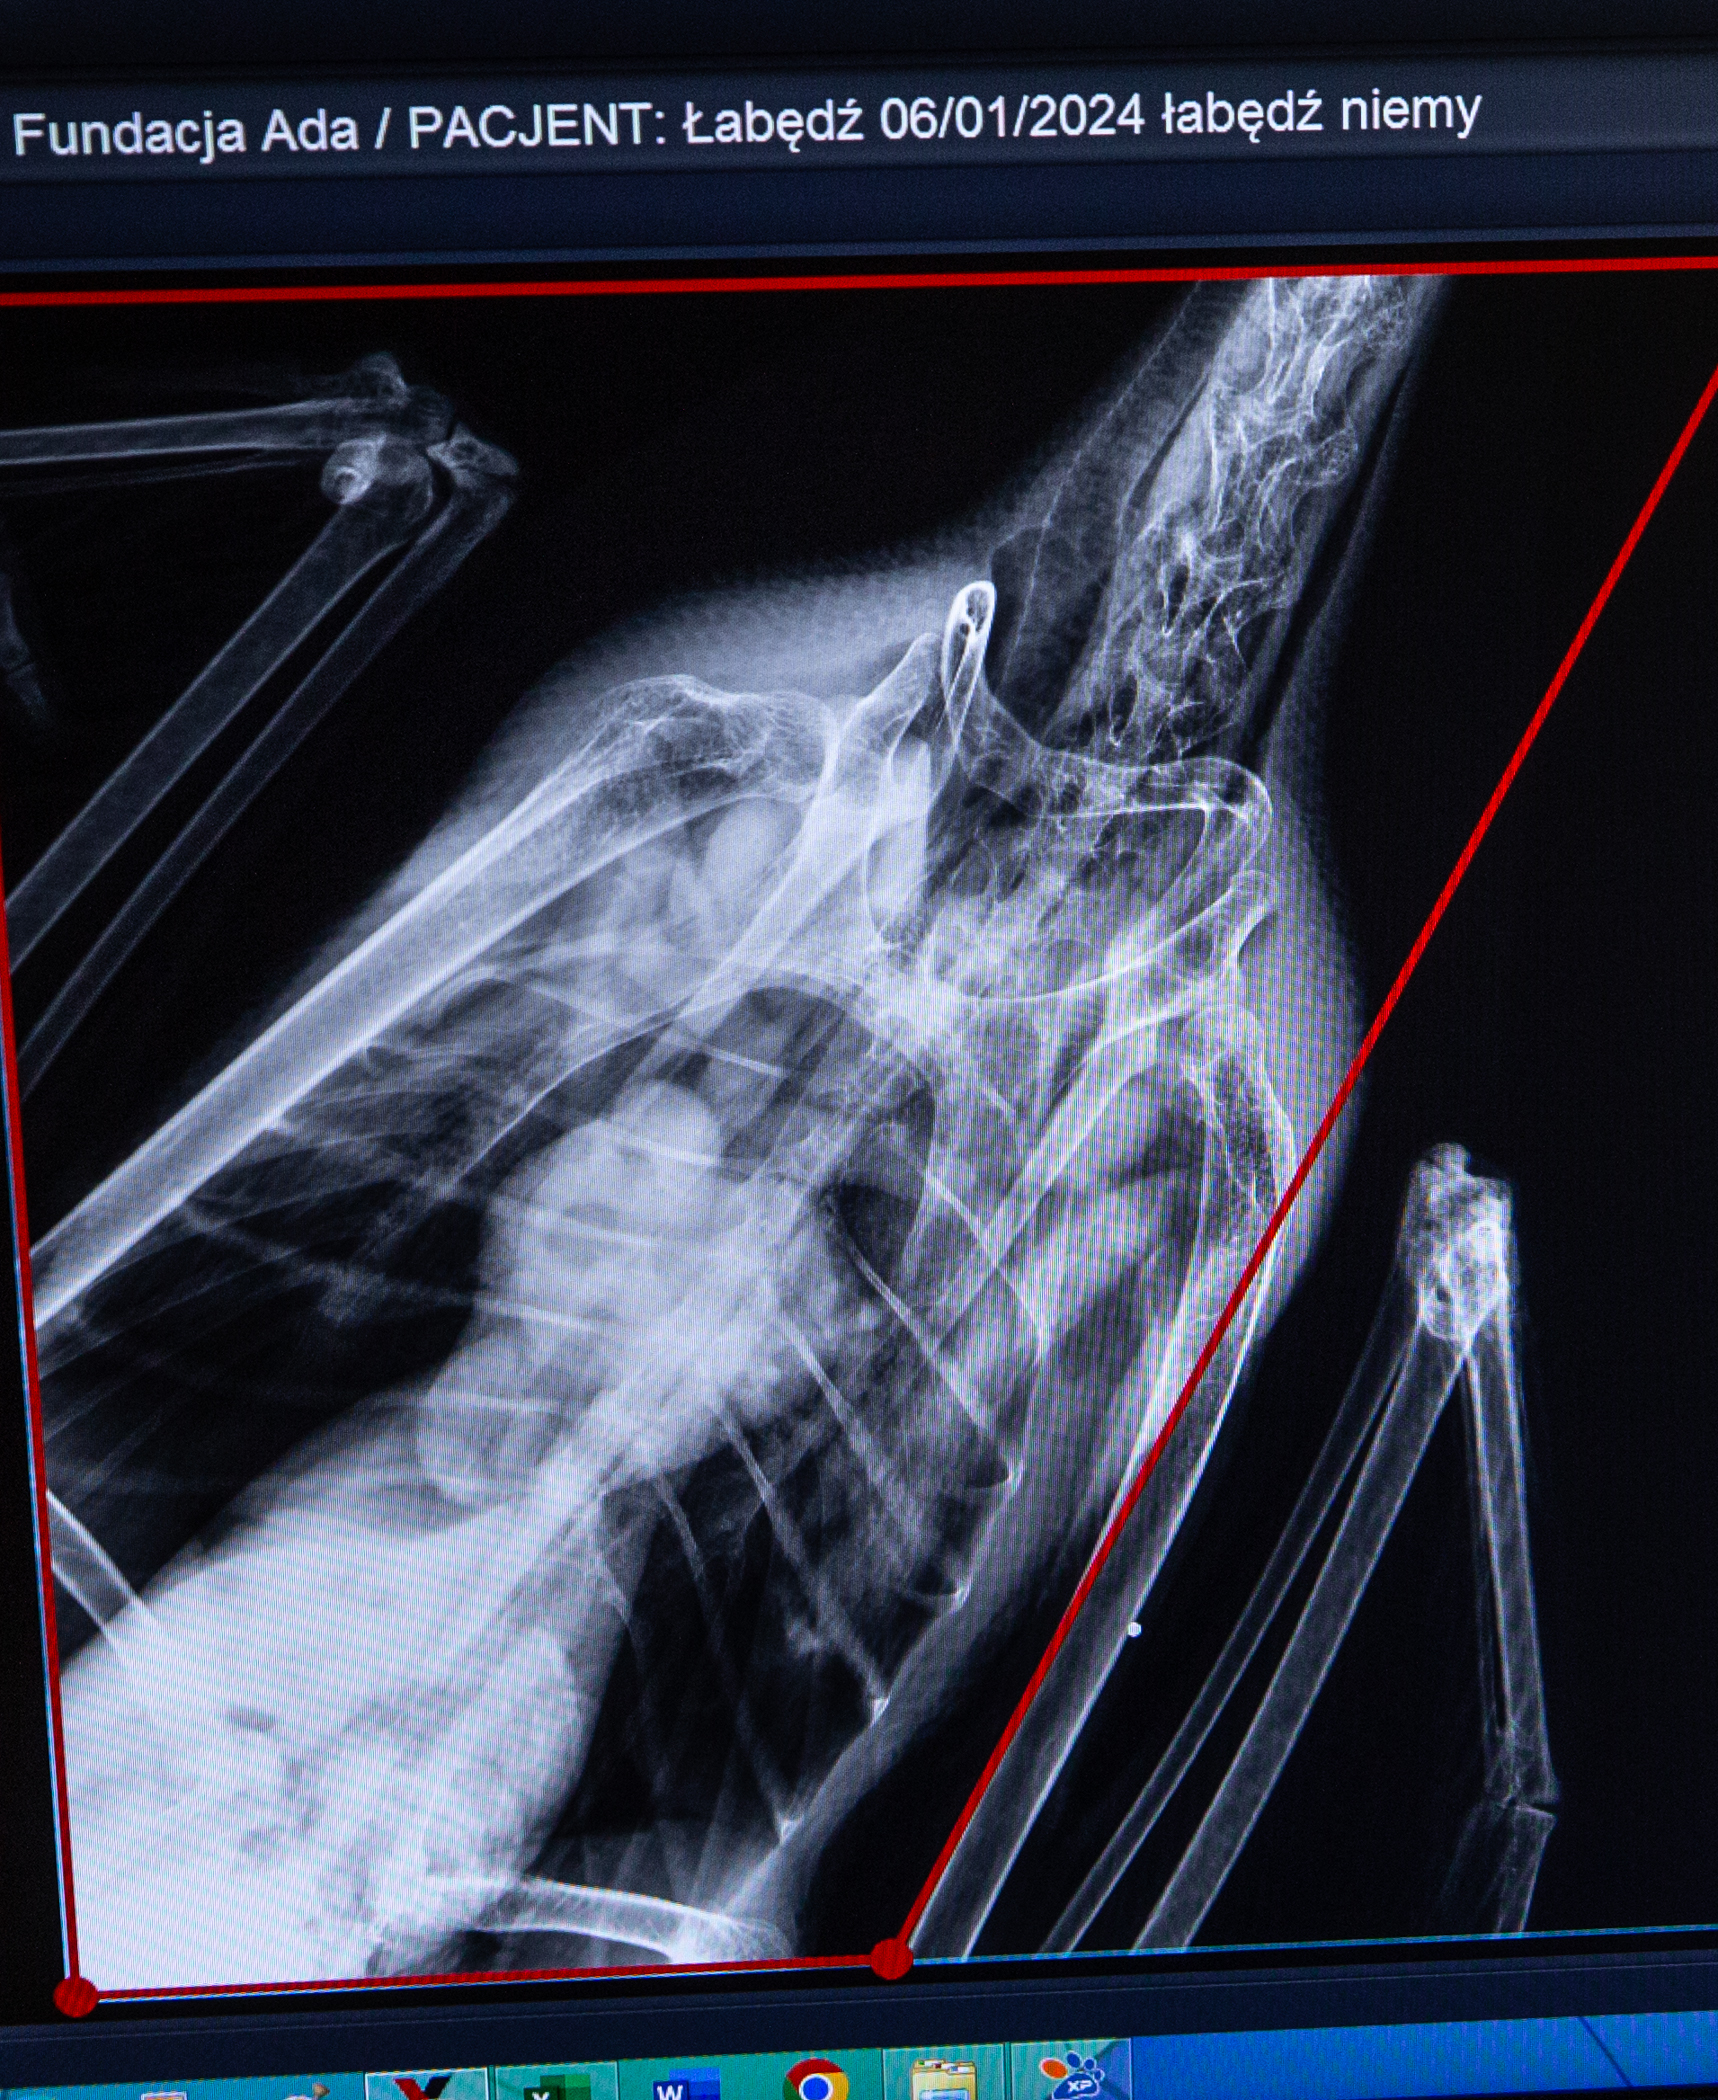

Oli Łabędź Ptak królewski brutalnie postrzelony przed zwyrodnialca trafił po ratunek do Fundacji ADA w stanie ciężkim. Dwa śruty ciało obce zakrwawione wycieńczone bólem i urazami Zwierzę z trudem oddychało kryjąc się polach.